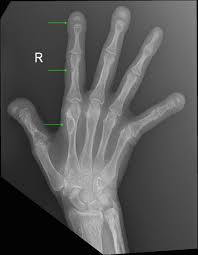

Radyolojik Görünüm

- En erken ve tipik bulgu:

➤ 2. ve 3. parmak orta falankslarının radial yüzlerinde subperiostal rezorbsiyon. - Klasik yerleşim:

- Falanks radial kenarları

| Patognomonik bölge | 2. ve 3. parmak orta falanks radial yüzleri |

| Radyolojik yerleşim | Falanks radial yüzleri (2.–3.) |